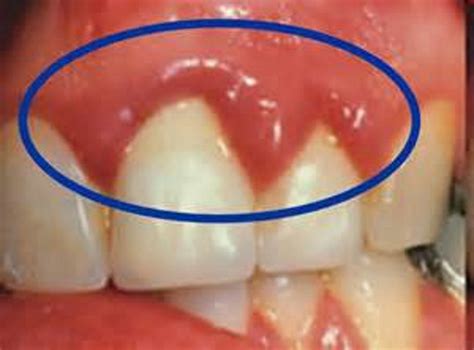

Gum boils, also known as periodontal abscesses or gum abscesses, are localized infections that occur in the gums. They are typically characterized by a small, pus-filled bump that can be quite painful. These boils can develop due to various reasons, including poor oral hygiene, trauma to the gums, or underlying dental issues.

- Pus Discharge: A small, pus-filled bump may be visible on the gum line.

To better understand what gum boils look like, it can be helpful to view pictures of gum boils. These visual aids can provide a clearer picture of the condition and help in identifying it. While it's important to note that pictures of gum boils can be graphic, they serve as valuable educational tools.